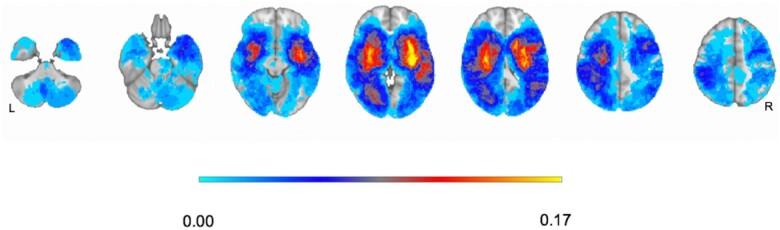

Neurological deficits following stroke are traditionally described as syndromes related to damage of a specific area or vascular territory. Recent studies indicate that, at the population level, post-stroke neurological impairments cluster in three sets of correlated deficits across different behavioural domains. To examine the reproducibility and specificity of this structure, we prospectively studied first-time stroke patients ( = 237) using a bedside, clinically applicable, neuropsychological assessment and compared the behavioural and anatomical results with those obtained from a different prospective cohort studied with an extensive neuropsychological battery. The behavioural assessment at 1-week post-stroke included the Oxford Cognitive Screen and the National Institutes of Health Stroke Scale. A principal component analysis was used to reduce variables and describe behavioural variance across patients. Lesions were manually segmented on structural scans. The relationship between anatomy and behaviour was analysed using multivariate regression models. Three principal components explained ≈50% of the behavioural variance across subjects. PC1 loaded on language, calculation, praxis, right side neglect and memory deficits; PC2 loaded on left motor, visual and spatial neglect deficits; PC3 loaded on right motor deficits. These components matched those obtained with a more extensive battery. The underlying lesion anatomy was also similar. Neurological deficits following stroke are correlated in a low-dimensional structure of impairment, related neither to the damage of a specific area or vascular territory. Rather they reflect widespread network impairment caused by focal lesions. These factors showed consistency across different populations, neurobehavioural batteries and, most importantly, can be described using a combination of clinically applicable batteries (National Institutes of Health Stroke Scale and Oxford Cognitive Screen). They represent robust behavioural biomarkers for future stroke population studies.

传统上,中风后的神经功能缺损被描述为与特定区域或血管区域损伤相关的综合征。最近的研究表明,在人群层面,中风后的神经功能障碍在不同行为领域的三组相关缺损中聚集。为了检验这种结构的可重复性和特异性,我们使用床边临床适用的神经心理学评估方法,对首次中风患者(n = 237)进行了前瞻性研究,并将行为和解剖学结果与另一组使用广泛神经心理学测试组合进行研究的前瞻性队列所获得的结果进行了比较。中风后1周的行为评估包括牛津认知筛查和美国国立卫生研究院中风量表。使用主成分分析来减少变量并描述患者之间的行为差异。在结构扫描上手动分割病变。使用多元回归模型分析解剖结构与行为之间的关系。三个主成分解释了约50%的受试者行为差异。主成分1与语言、计算、实践、右侧忽视和记忆缺陷相关;主成分2与左侧运动、视觉和空间忽视缺陷相关;主成分3与右侧运动缺陷相关。这些成分与使用更广泛测试组合获得的成分相匹配。潜在的病变解剖结构也相似。中风后的神经功能缺损在低维度损伤结构中相关,既与特定区域或血管区域的损伤无关。相反,它们反映了由局灶性病变引起广泛的网络损伤。这些因素在不同人群、神经行为测试组合中表现出一致性,最重要的是,可以使用临床适用测试组合(美国国立卫生研究院中风量表和牛津认知筛查)进行描述。它们代表了未来中风人群研究中强大的行为生物标志物。